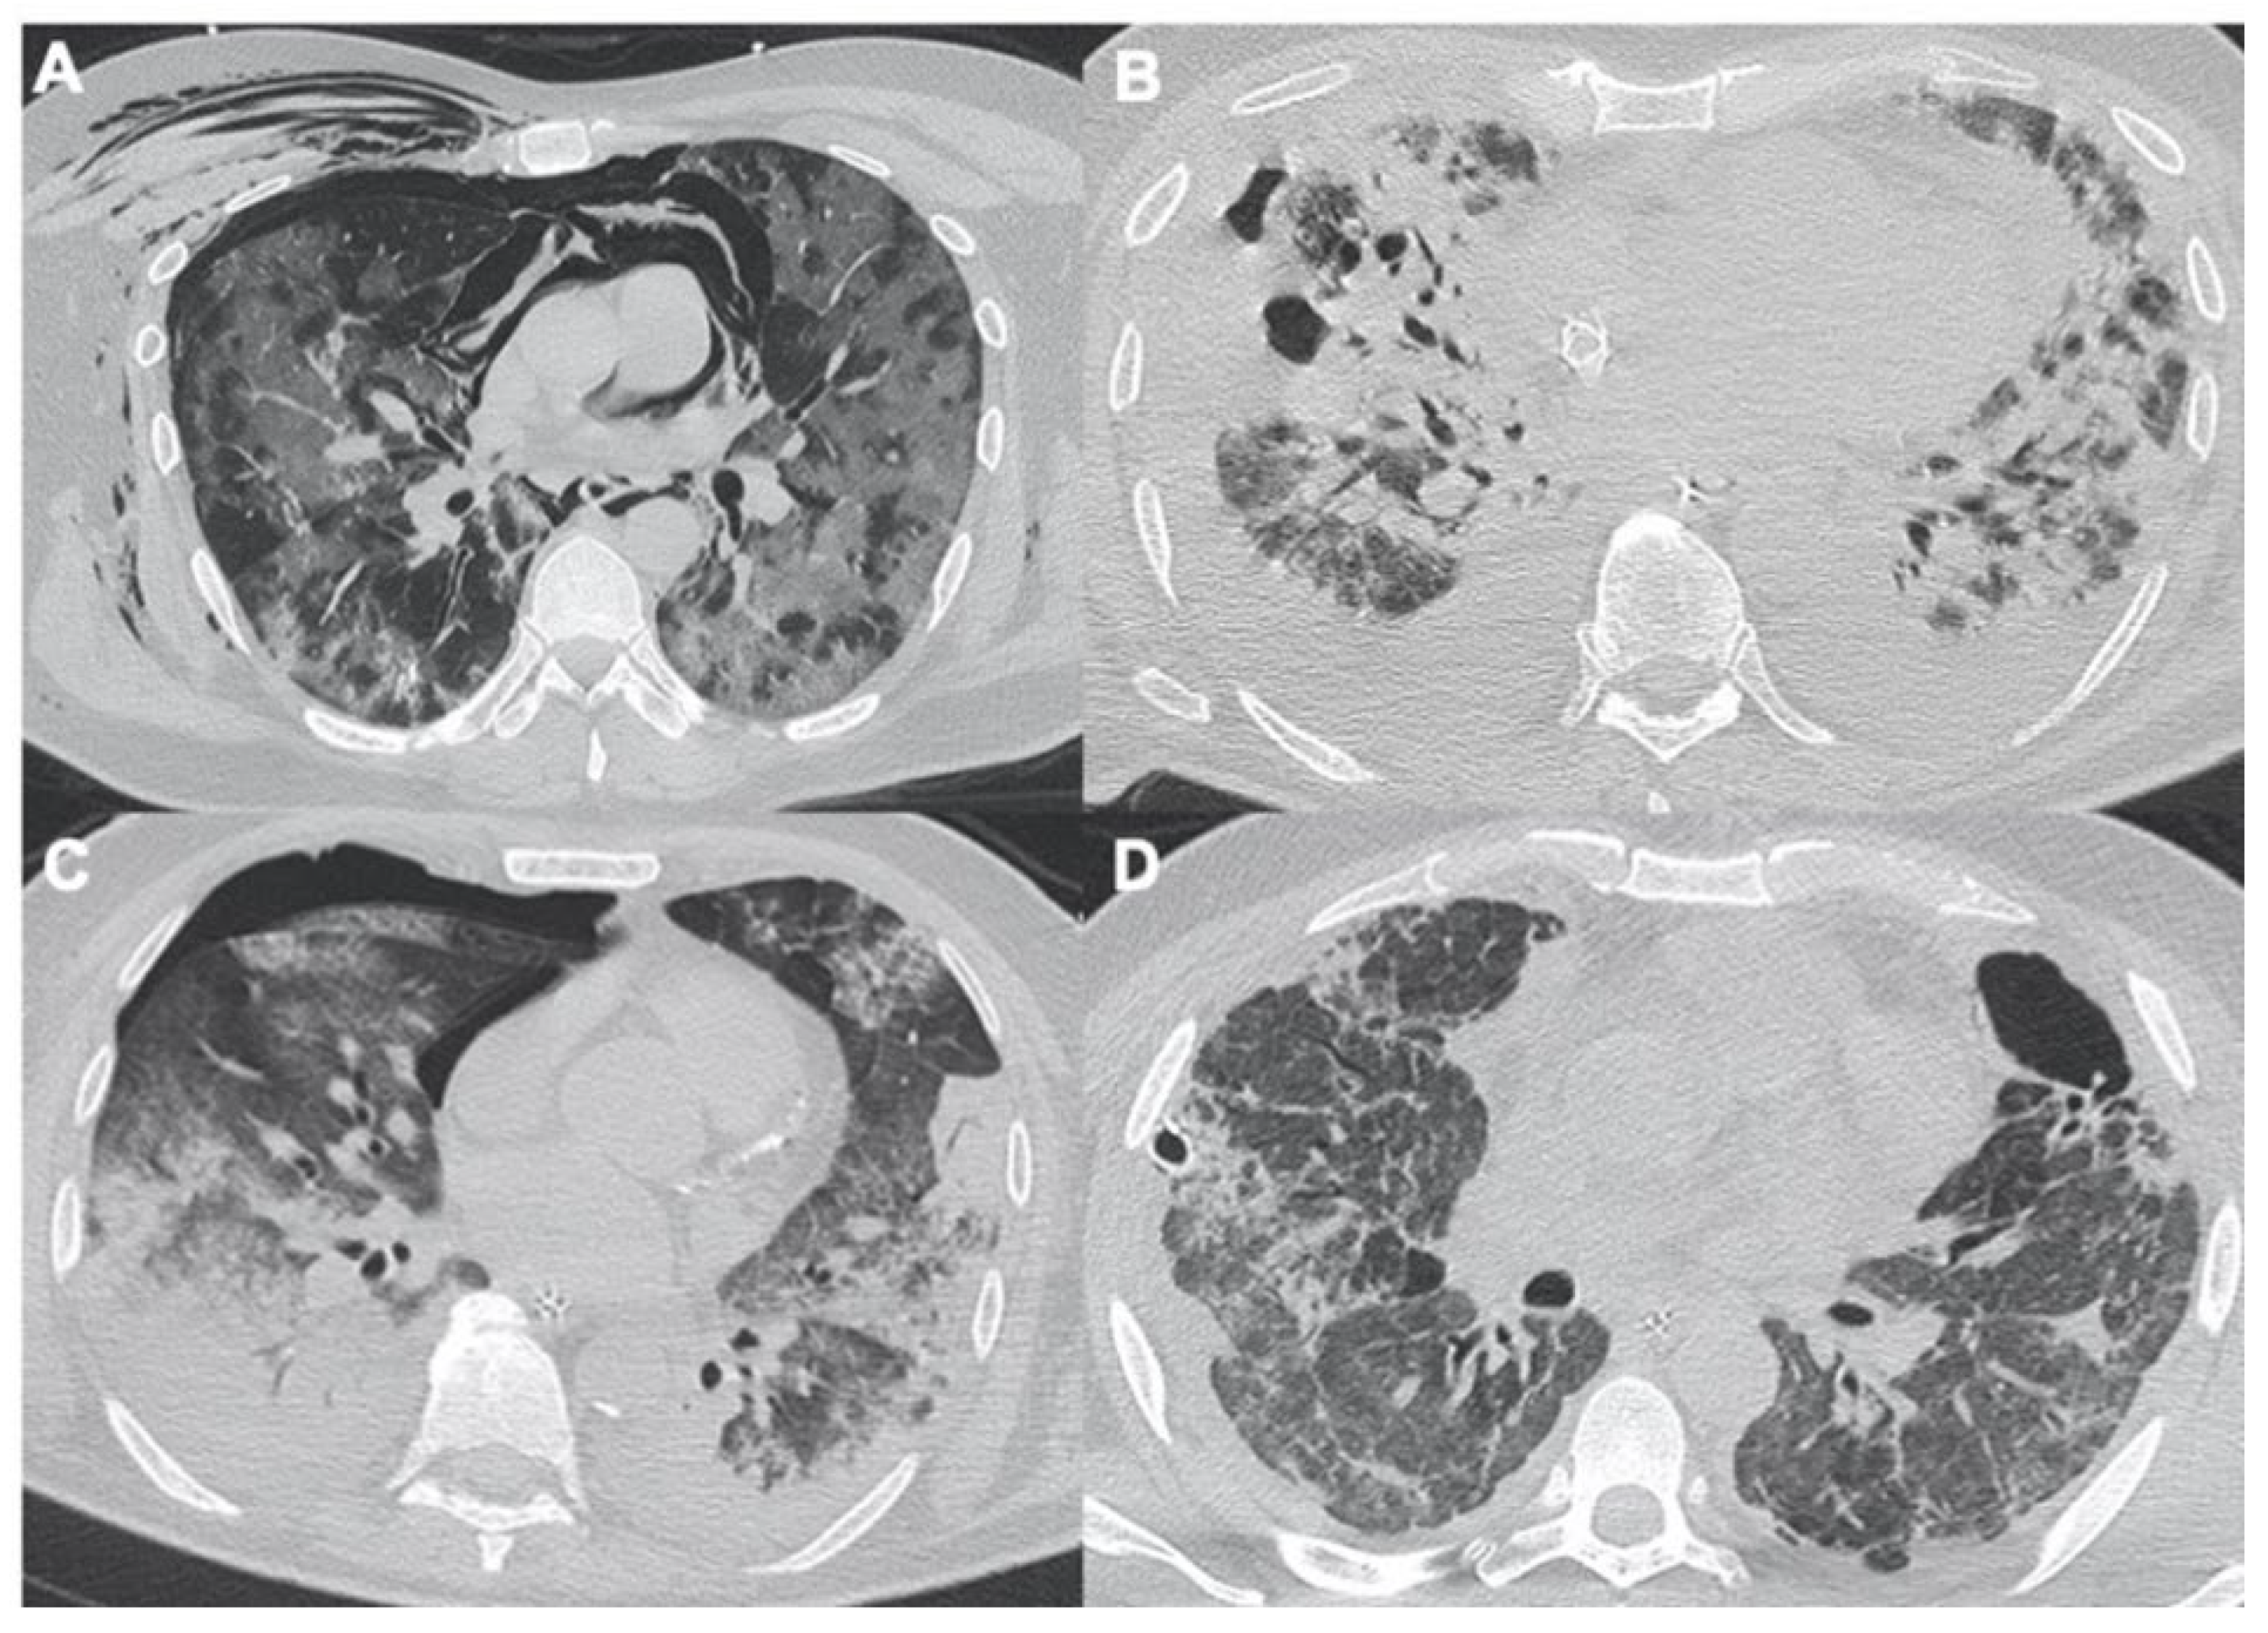

2.2. Acute Respiratory Disease Syndrome